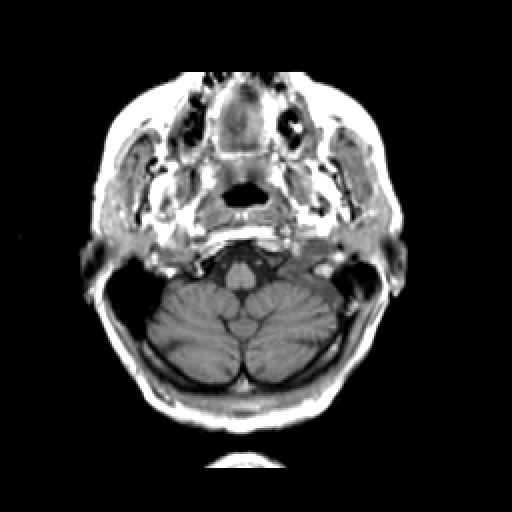

T1-weighted structural MR: Slice 7

Slice 7